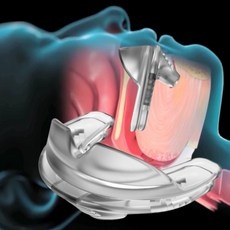

현재 코골이와 수면무호흡증에 대한 비수술 치료로는 양압기 치료가 세계적으로 권고되고 있다. 스페인 페셋박사대학병원 마리나 카라스코 야타스(Marina Carrasco-Llatas) 교수팀에 따르면, 폐쇄성수면무호흡증은 양압기 치료가 매우 효과적이다. 연구팀에 따르면, 상부기도를 열어 호흡 흐름을 원활하게 해주는…

양압기는 대부분의 수면무호흡증이나 코골이 개선에 많은 도움이 되는 장치다. 양압기는 일정한 압력으로 공기를 불어 넣어 상기도가 좁아지거나 닫히지 않도록 도와주는 의료기기다. 개개인의 상태에 가장 적합한 압력을 찾아 가동해야 치료 효과를 높일 수 있으므로 반드시 의료진과 상담하여 양압기 처방을…

수면무호흡증에 의한 수면의 질 저하는 양압기 사용이 일반적인 치료법이다. 양압기 치료는 상기도에 일정한 압력의 공기를 주입하여 수면 중 기도가 막히거나 좁아지는 것을 예방해주어 주간 졸림 등의 증상 개선과 더불어 심혈관 질환과 뇌혈관 질환의 치료에 중요한 역할을 한다. 대한수면호흡학회 교육이사인…

치료는 양압기 치료다. 기계에서 공기를 공급해 압력을 가하면 좁아지는 기도를 열어주고 폐를 펴주는 것과 함께 심장도 짜주는 효과를 낸다. 수면다원검사 결과 수면무호흡증을 진단받으면 보험 적용으로 월 2만 원 미만의 본인 부담금으로 치료를 받을 수 있다. 처음 양압기를 접하면 그 생김새와 평생 사용해야…

비수술적 치료이자 1차 치료법인 양압기 치료는 코에 공기를 불어넣고 기도 내 공기 압력을 높여 기도가 폐쇄되지 않도록 한다. 다만 양압기를 사용하지 않으면 수면무호흡증에 다시 노출되기에 매일 잠자는 동안 꾸준히 양압기를 착용하는 게 중요하다. 그런데 양압기 착용이 번거로워 적지 않은 환자(30~40%)가…

연구팀은 수면무호흡증 환자의 인지기능장애 치료는 그 방법에 따라 다양하지만, 지속적인 양압기 요법이 가장 효과적이라고 강조했다. 연구팀은… 현재 코골이나 수면무호흡증에 대한 일차치료에는 비수술법 요법인 양압기 치료가 권고되고 있다. 양압기는 안전하고 효과의 적용 범위가 넓으면서 부작용이…

비수술적 치료이자 1차 치료법인 양압기 치료는 코에 공기를 불어넣고 기도 내 공기 압력을 높여 기도가 폐쇄되지 않도록 하는 것이다. 미국 수면학회에서는 심혈관장애를 겪거나 고위험자에게는 1차적으로 양압기 치료를 권장한다. 양압기 전문 요원이 있는 병원에서 의사 조언에 따라 훈련해야 효과적으로…